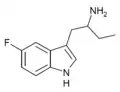

List of substituted α-alkyltryptamines

α-Alkyltryptamines are a group of substituted tryptamines which possess an alkyl group, such as a methyl or ethyl group, attached at the alpha carbon, and in most cases no substitution on the amine nitrogen.[17][18][19] α-Alkylation of tryptamine makes it much more metabolically stable and resistant to degradation by monoamine oxidase, resulting in increased potency and greatly lengthened half-life.[19] This is analogous to α-methylation of phenethylamine into amphetamine.[19]

Many α-alkyltryptamines are drugs, acting as monoamine releasing agents, non-selective serotonin receptor agonists, and/or monoamine oxidase inhibitors,[20][21][22][23] and produce psychostimulant, entactogen, and/or psychedelic effects.[17][18][19] The most well-known of these agents are α-methyltryptamine (αMT) and α-ethyltryptamine (αET), both of which were used clinically as antidepressants for a brief period of time in the past and are abused as recreational drugs.[18][19] In accordance with its action as a dual releasing agent of serotonin and dopamine, αET has been found to produce serotonergic neurotoxicity similarly to amphetamines like MDMA and PCA, and the same is also likely to hold true for other serotonin and dopamine-releasing α-alkyltryptamines such as αMT, 5-MeO-αMT, and various others.[24]

5-Fluoro-αMT | 1-(5-fluoro-1H-indol-3-yl)propan-2-amine | 712-08-3 |

5-Fluoro-αET | 1-(5-fluoro-1H-indol-3-yl)butan-2-amine | 1380137-98-3 |